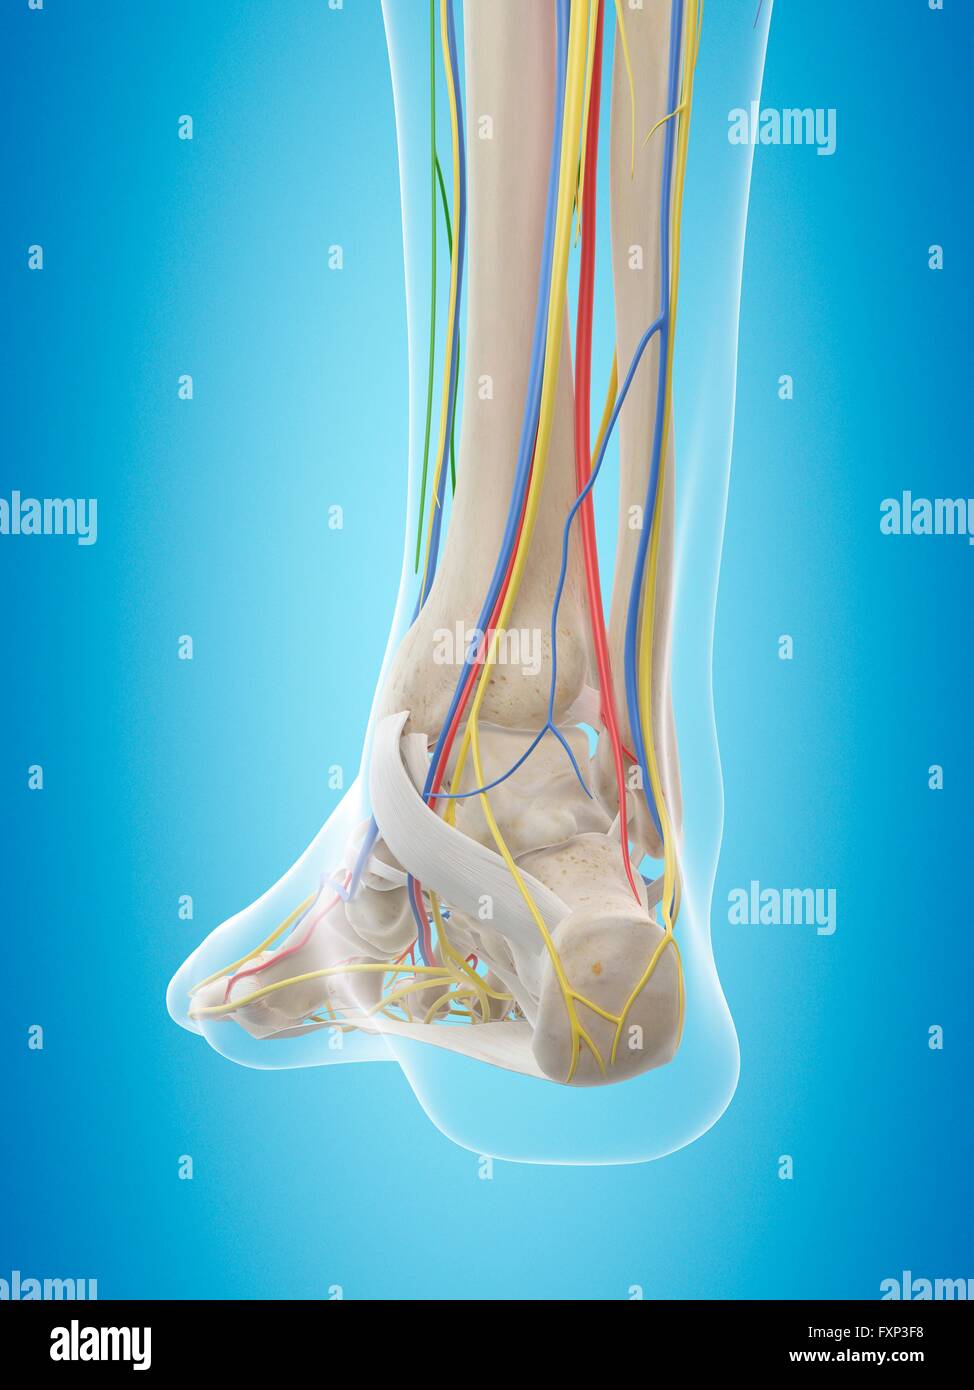

RFTCW7GT–L'articulation de la cheville, les tendons de la cheville anatomie pied eps vector illustration infographie 10